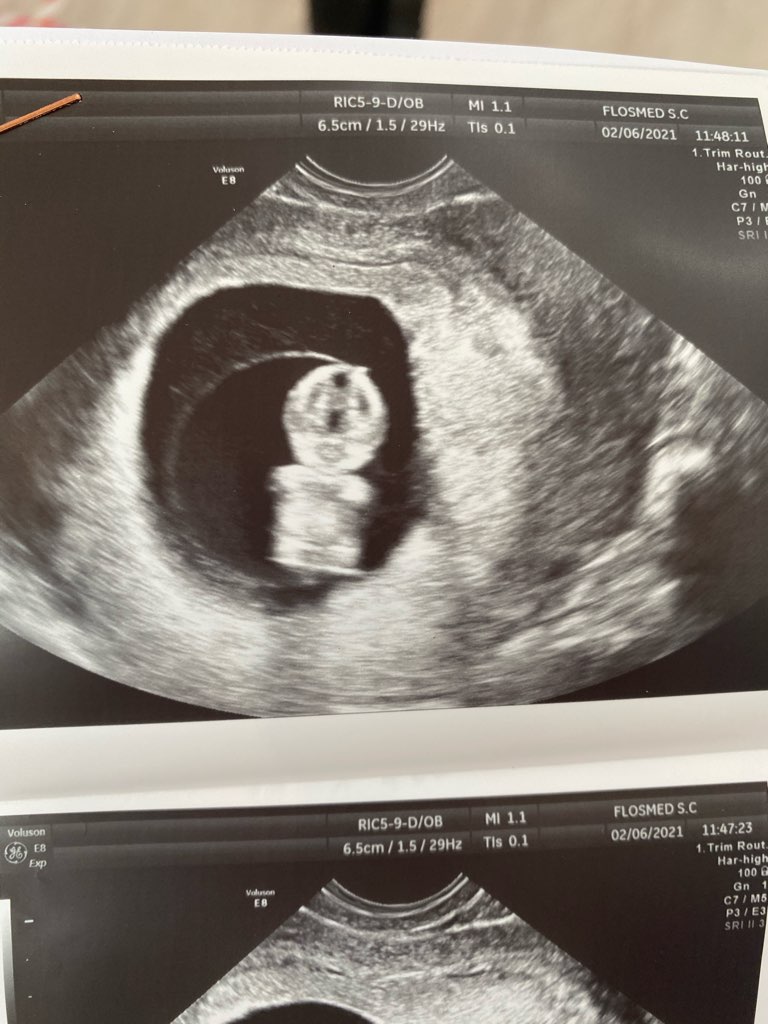

A ja zaczne temat, która z Was jest w 11tc? I ile mierzą wasze maluszki?![]()